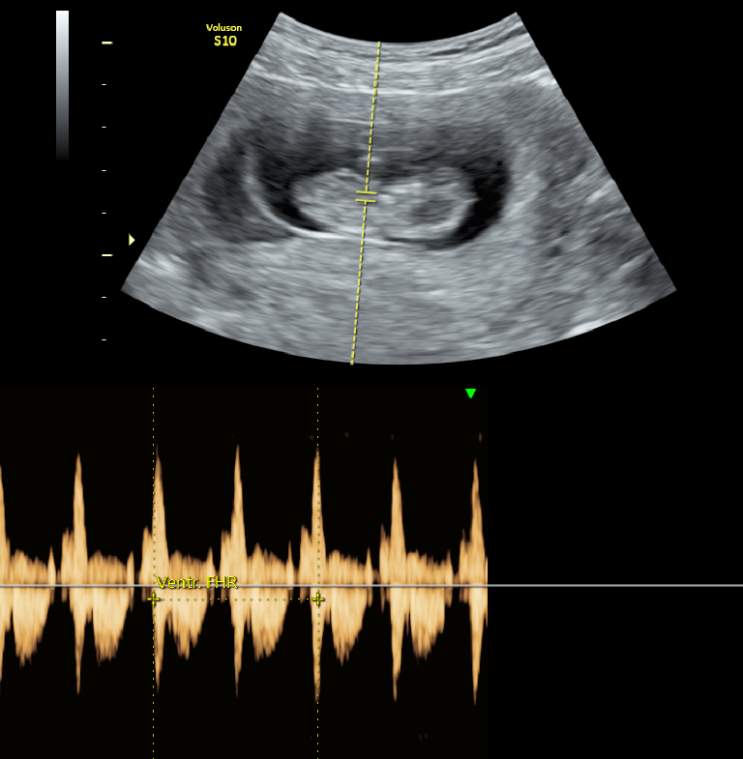

타원에서 신선배아이식 3회와 동결배아이식 2회를 받으셨으나 결과가 좋지 않아 올해 4월에 미래연에 처음 ...

첫째와 둘째를 모두 인공수정으로 임신하신 분입니다. 2019년에 임신이 잘 안되어 미래연에 처음 오셨습니...